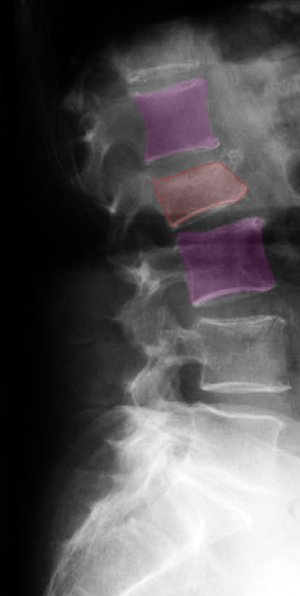

Κάταγμα 01 (φούξια) με μείωση του ύψους του σπονδύλου σε σύγκριση με τον υποκείμενο υγιή σπόνδυλο (μπλέ)(αριστερά). Κυφοπλαστική με ανάταξη του κατάγματος και επαναφορά του ύψους του σπονδύλου στο φυσιολογικό (δεξιά).